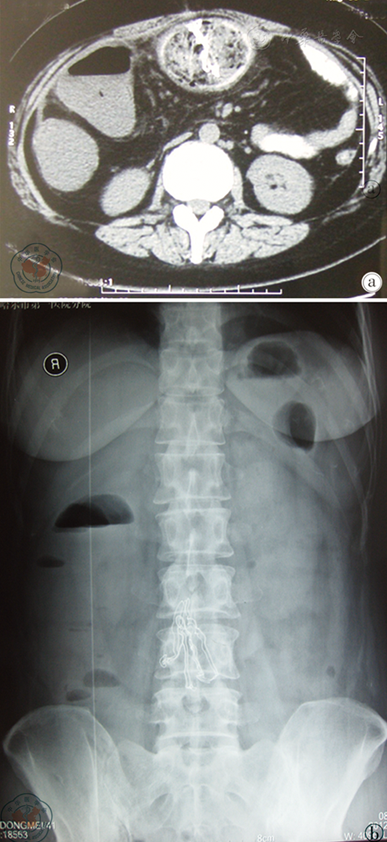

图1 肠梗阻患者术前腹部CT及X线平片检查图像